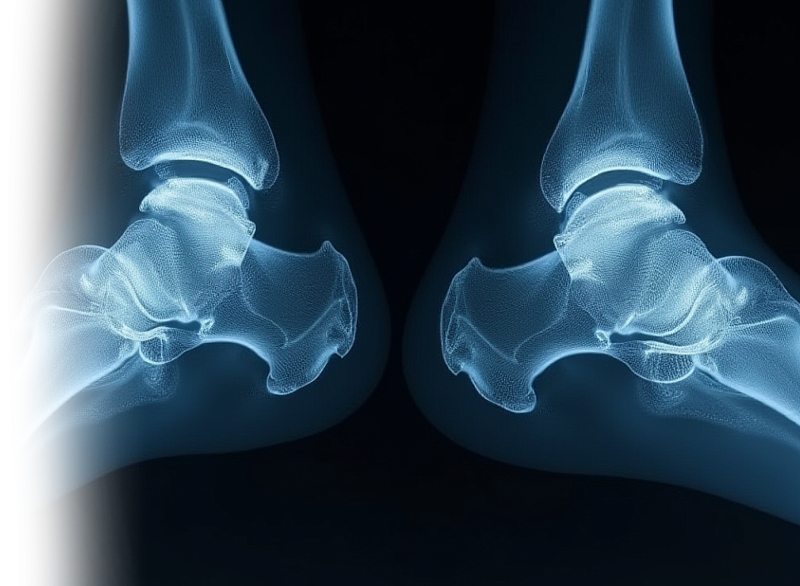

Компьютерная томография двух смежных суставов – важный метод исследования состояния двух смежных суставов (плечевые, тазобедренные, коленные, голеностопные).

При одновременном сканировании КТ позволяет сравнить два смежных сустава, а также исключить патологию сустава костно-травматического, дегенеративного характера, изменения опухолевого или воспалительного генеза. Также оцениваются окружающие сустав мягкие ткани (для более детальной оценки мягких тканей целесообразно МР-исследование суставов).